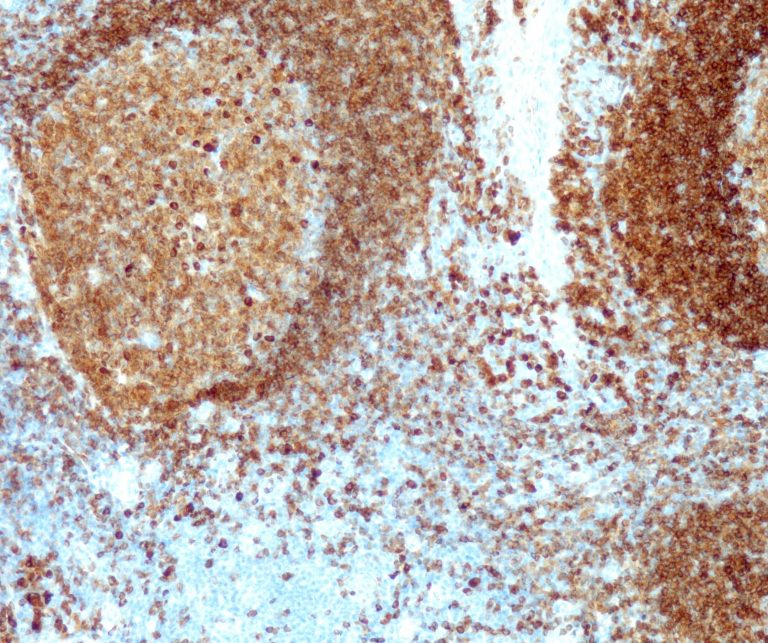

Vascular Pathology

Gastrointestinal (GI) Pathology

General Marker

Breast Pathology

Endocrine Pathology

Gynecological Pathology

Neuropathology

Infection Markers

Lung Pathology

Urinary Tract Pathology

Transplantation Pathology

Soft Tissue Pathology

Hematopathology